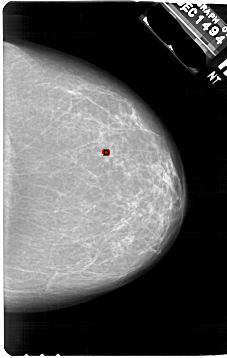

A_1751_1.LEFT_MLO

LEFT_MLO LINES 6826 PIXELS_PER_LINE 4591 BITS_PER_PIXEL 12 RESOLUTION 43.5 NON_OVERLAY

FILE: A_1751_1.RIGHT_MLO.OVERLAY

TOTAL_ABNORMALITIES 1

ABNORMALITY 1

LESION_TYPE CALCIFICATION TYPE PLEOMORPHIC DISTRIBUTION CLUSTERED

ASSESSMENT 4

SUBTLETY 2

PATHOLOGY BENIGN

TOTAL_OUTLINES 1

BOUNDARY